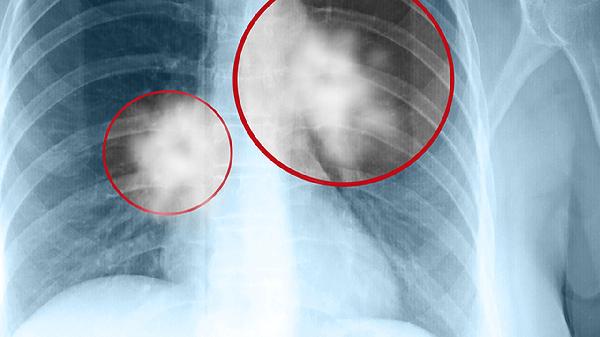

少量胸腔积液经对症治疗约2-4周可吸收,中至大量积液需4-6周引流配合药物治疗。恶性胸腔积液因持续渗出可能需反复治疗。

结核性胸膜炎需规范抗结核治疗6-9个月;心衰引起的积液需控制心功能后逐渐消退;肿瘤转移性积液需原发病控制后才可能缓解。